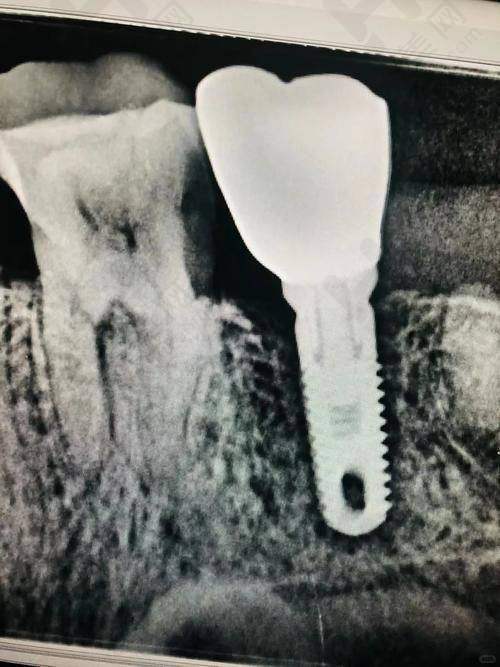

在服务项目方面,丰台院区提供了完善的口腔医疗服务。涵盖了日常口腔护理,像牙齿清洁、牙结石去除、牙齿美白等;牙齿修复项目,如补牙、牙冠、牙桥等;牙齿矫正服务,包括隐形矫正、传统矫正等;还有种植牙服务,为牙齿缺失患者带来福音。此外,医院还设有多个口腔科室,如口腔颌面外科、牙周科、儿童口腔科等。

海淀院区同样提供全方面的口腔医疗服务,包括日常口腔护理、牙齿修复、牙齿矫正、种植牙以及各类口腔科室的服务。患者反馈海淀院区的医生态度友好,服务周到,设备齐全,在治疗过程中患者能感到舒适。其营业时间为周一至周日08:30 - 17:30 ,方便患者随时就诊。

在设备方面,医院引进了精良的口腔医疗设备,这些设备能够提高诊断的正确性和治疗的成效,为患者的口腔健康提供有力保护。